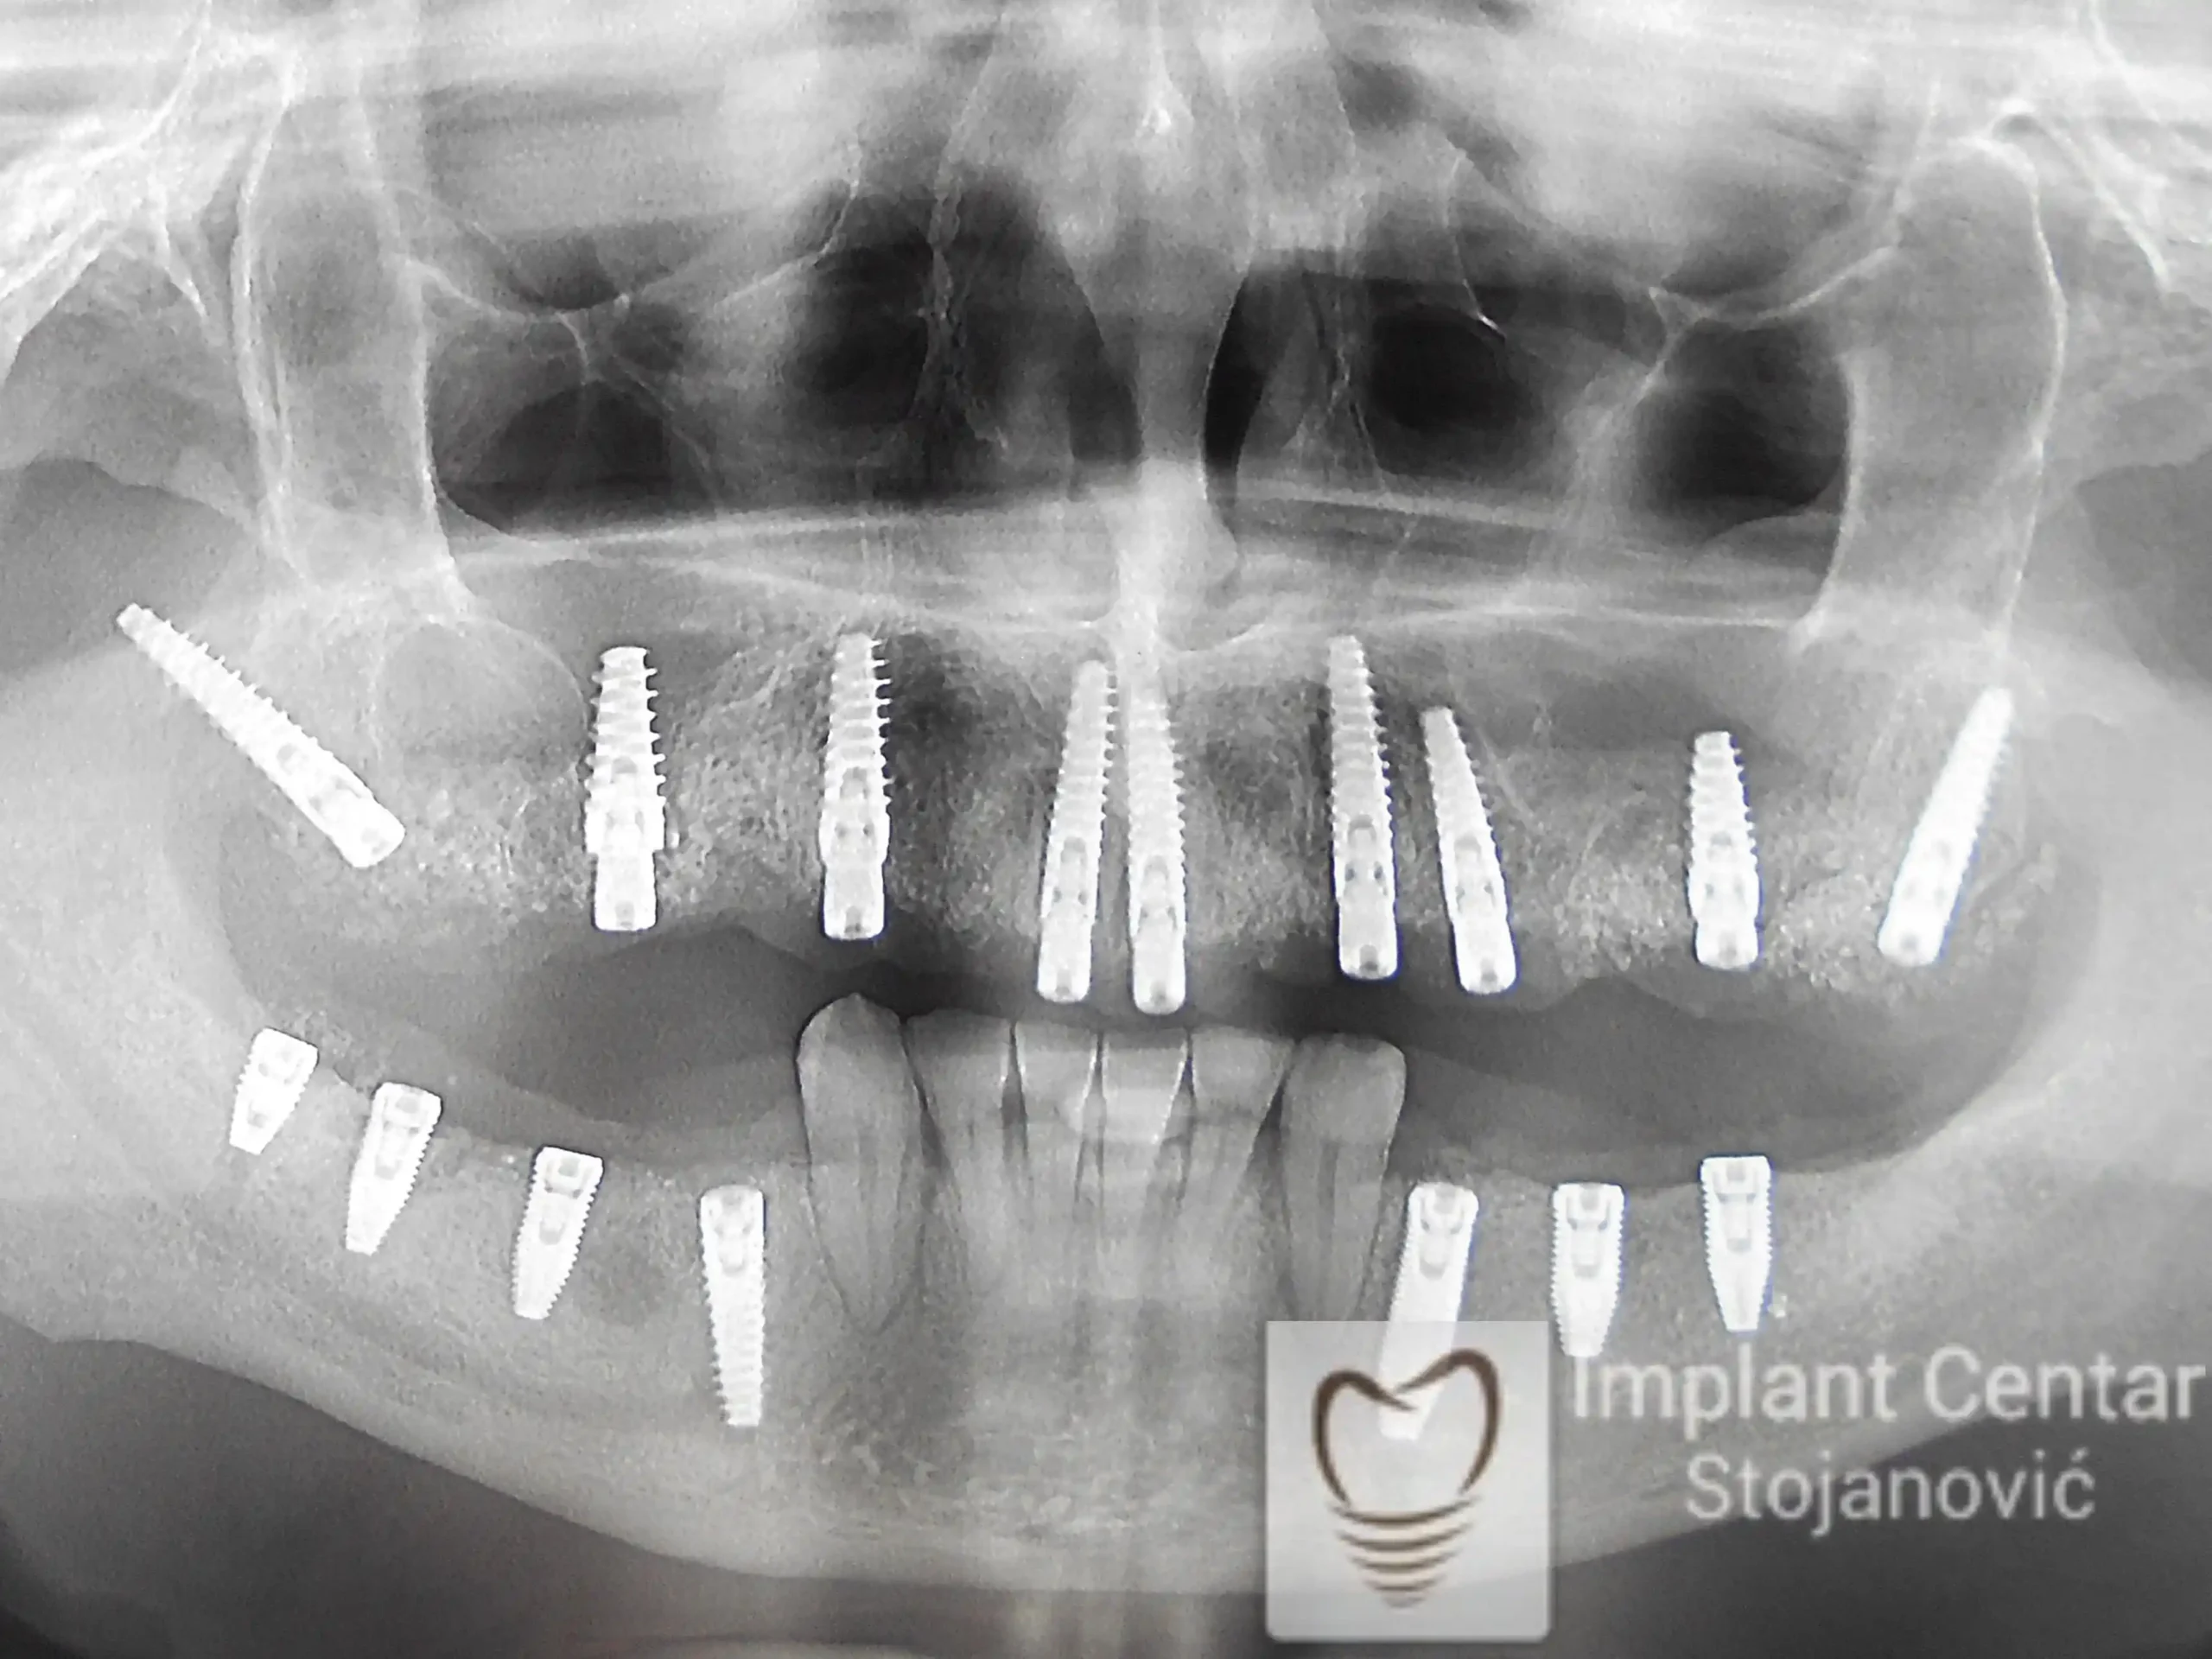

Na slici 1. i slici 2. prikazan je izgled pacijenta pre početka terapije – klinički i rendgenološki.

Nakon vađenja zuba, ugrađeni su implantati. Na slici 3 prikazan je ortopan snimak sa ugrđenim implantatima. Tokom perioda osteointegracije, pacijent je bio zbrinut fiksnim privremenim krunicama na implantatima, koje su izrađene samo dva dana nakon hirurške intervencije.